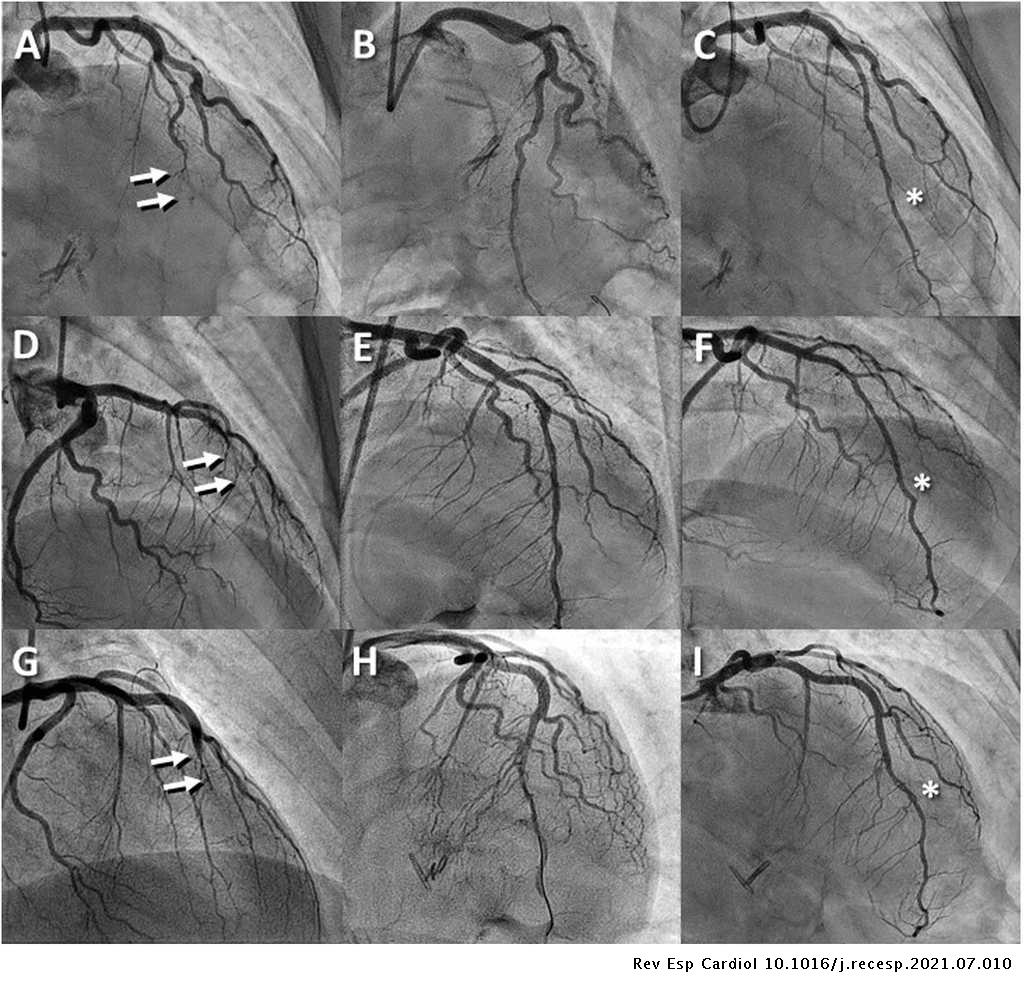

Nuestra experiencia en pacientes con #SCAD inestables que precisan intervencionismo: fenestración como opción. Excelentes resultados a corto y medio plazo. Son pacientes consecutivos!! No hemos excluido ninguno @fer_iver @CCuesta2 @David_delVal_ @enferhemo

Treatment of spontaneous coronary artery dissection with fenestration: clinical and angiographic follow-up Tratamiento de la disección coronaria espontánea con fenestración: evolución clínica y angiográfica #AheadOfPrint #REC #Cardiotwitter https://t.co/7Aoq16OPSc